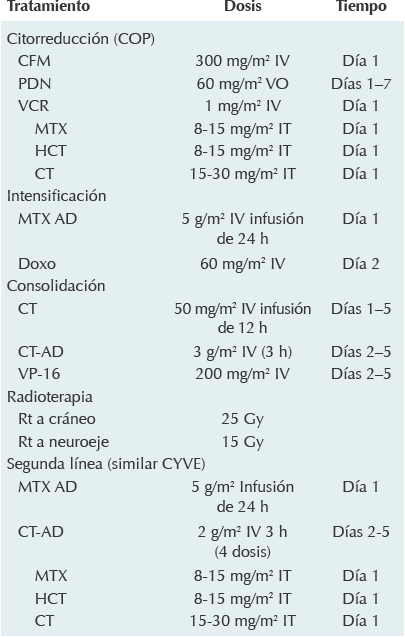

Se inició tratamiento de quimioterapia con fase de citorreducción similar al linfoma no Hodgkin de células B. 9,10,20 Al final de esta fase la paciente tuvo datos de hipertensión intracraneana que se clasificó como enfermedad estable. Se continuó el tratamiento de intensificación20,21 con adriamicina y dosis altas de metotrexato, a pesar de lo cual la paciente mostró progresión de la enfermedad por lo que se inició la fase de consolidación (similar al CYVE 1)10 que se modificó de acuerdo con las condiciones clínicas de la paciente. El tratamiento quimioterapéutico se resume en el Cuadro 2.

CFM: ciclofosfamida; PDN: prednisona; VCR: vincristina; HCT: hidrocortisona; MTX: metotrexato; MTX-AD: metotrexato en dosis altas; Doxo: doxorrubicina; CT: citarabina; CT-AD: citarabina en dosis altas; VP-16: etopósido; Rt: radioterapia.

Cuadro 2 Esquema del tratamiento administrado